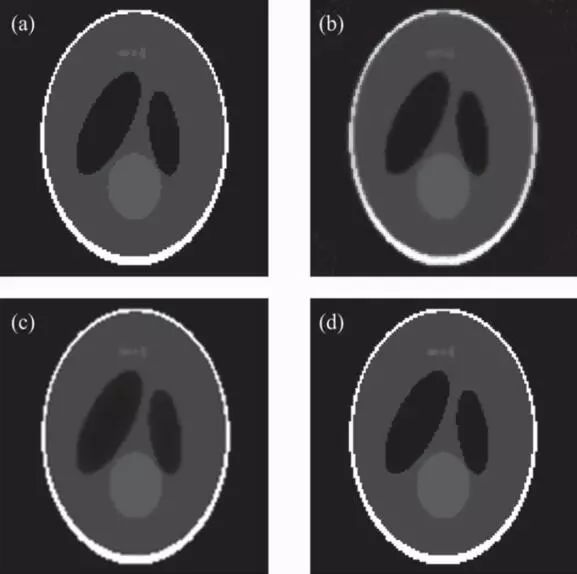

实验结果表明:与解析重建算法FDK相比,提出的算法在投影数较少的情况下,仍能获得较好的重建图像质量(见图1);与两种现有的基于TV正则化的迭代重建算法(ASD-POCS,EM-TV)相比,所提算法收敛速度提高6倍以上,且表现出更强的图像去噪和边缘保持能力(见图2)。此外,采用GPU加速手段使得上述迭代算法的重建时间大为减少(见表1)。

图2. 经典迭代算法与3DA-TVAL3算法的重建结果。(a)Sheep-Logan体模的原图像;(b)ASD-POCS算法的重建结果;(c)EM-TV算法的重建结果;(d)3DA-TVAL3算法的重建结果。